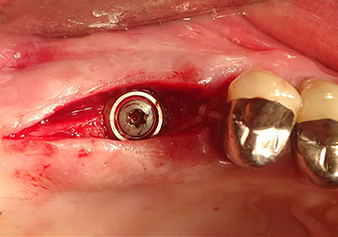

The I2A instrument (diameter 2.0 mm) was then used to perforate the sinus floor intermittently and on the smallest scale possible. This special piezosurgical method ensures that the Schneiderian membrane is not damaged. When the Z25P was used, the membrane was already lifted slightly by the coolant supplied via the instrument tip (Fig. 3). The coolant quantity was just 50% in order to avoid high pressure in the implant bed.

The Schneiderian membrane is carefully detached with the Z25P instrument (phase 1)

Fig.3: Following marking of the implant position and initial expansion of the bed, the Schneiderian membrane is carefully detached with the Z25P instrument (phase 1).

The implant bed is widened to 3.0 mm with the I3A instrument

Fig.5: In the next step, the implant bed is widened to 3.0 mm with the I3A instrument (power 100%, coolant 80%). The depth marks reliably prevent the preparation from going too deep.